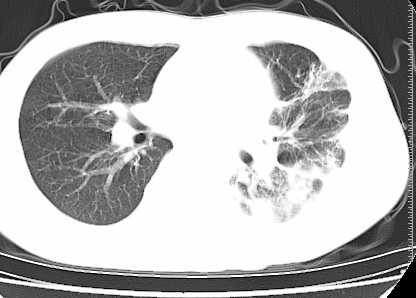

二周前患者无明显诱因出现咳嗽,多为刺激性干嗽,无咯血,伴心悸,低热,夜间无明显盗汗,消瘦明显

左下肺见有较多斑片状和大片状影,支气管通畅,左侧胸腔积液,考虑:左下肺炎伴胸腔积液

左侧中量胸腔积液伴左肺下叶肺膨胀不全、上肺外围多个小囊样腺泡样病灶。考虑化脓炎症。

首先考虑肺结核胸膜炎心包炎,胸水压迫性肺不张

患者刺激性干嗽,无咯血,伴心悸,低热,夜间无明显盗汗,消瘦明显,左侧中量胸腔积液伴左肺下叶肺膨胀不全、上肺外围多个小斑片病灶。考虑肺结核可能性大。

左肺舌叶及下叶见斑片状,大片状高密度影并相应处胸膜及心包不规则增厚,左肺下叶膨胀不全。右肺未见异常,双肺段以上支气管通畅。纵隔左移,其内未见明显肿大淋巴结。左侧胸腔积液。

1.考虑:左肺化脓性炎症。2.左侧胸腔积液(中等量)。3.心包炎症。

肺结核,结核性胸膜炎.